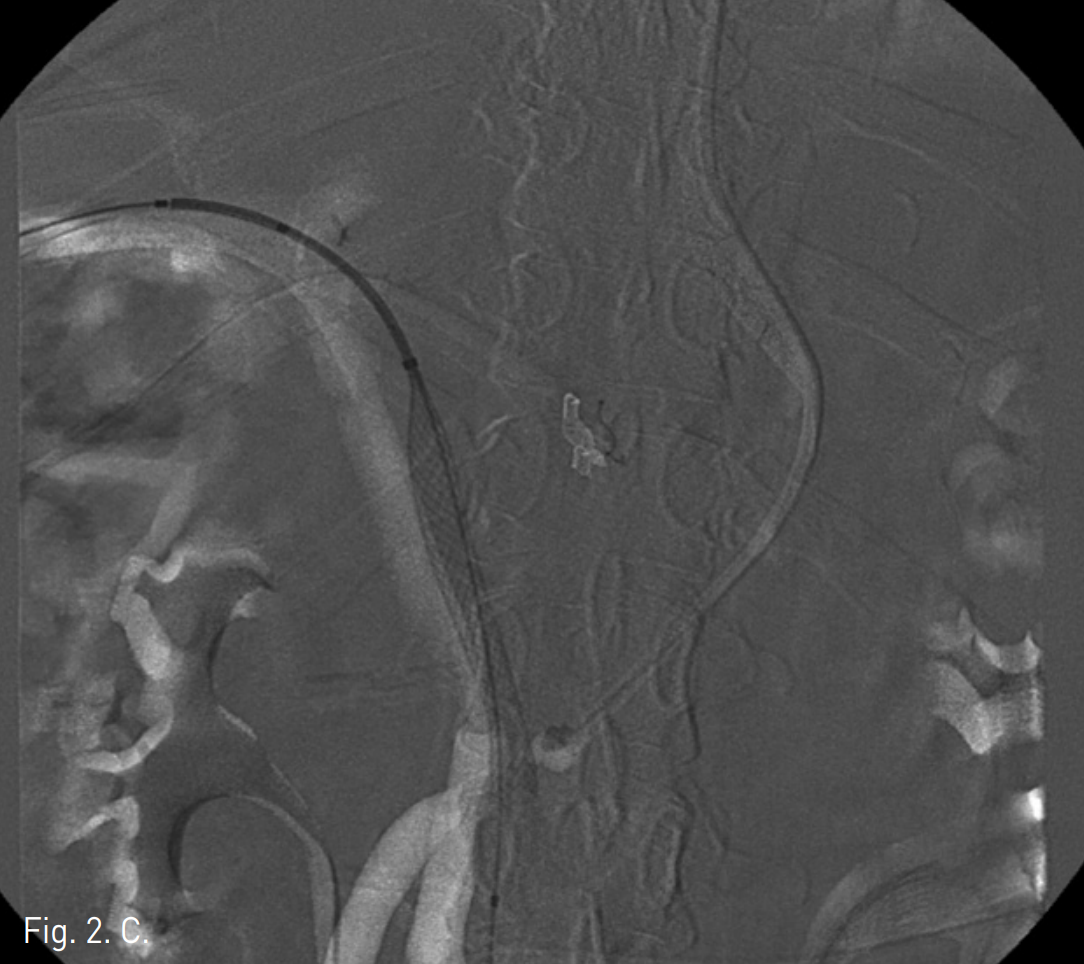

수술 후 7일째 시행한 복부 CT 문맥기에서 합성혈관(synthetic graft)이 혈전으로 막혀 있고(Fig. 1) 빈창자(jejunum)의 점막을 따라 조영 증강되는 정맥성 울혈이 보인다. 하지만 간 내 문맥의 혈류는 유지되고 있다.

Fig. 1

Coronal reconstruction image of CT scan shows thrombotic occlusion of synthetic graft por tal vein (arrows). But, the intrahepatic portal vein is patent (arrowhead).